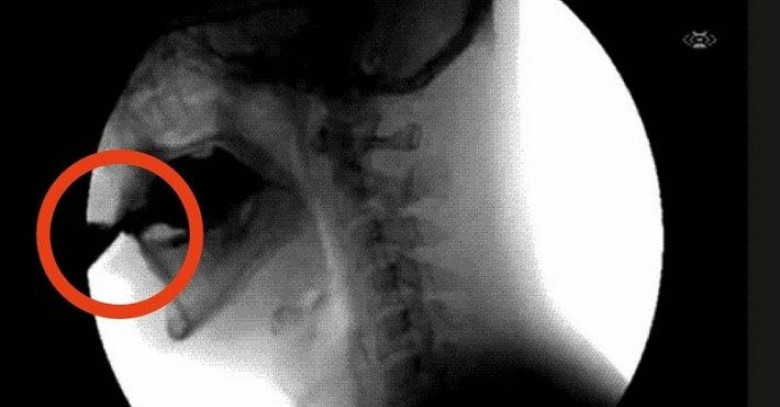

Употребление сладких газированных напитков — главная причина возникновения диабета и ожирения, но и это еще не всё. Фосфорная кислота, которая содержится в «Кока-коле», связывает кальций, магний и цинк в нижнем отделе кишечника, и они выводятся из организма в ускоренном режиме! А мы и так получаем недостаточное количество этих элементов с пищей… В результате кости становятся ломкими и ухудшается обмен веществ.